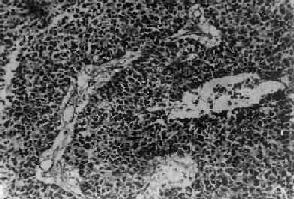

图13-27 乳腺髓样癌

癌细胞排列成片团状,间质少